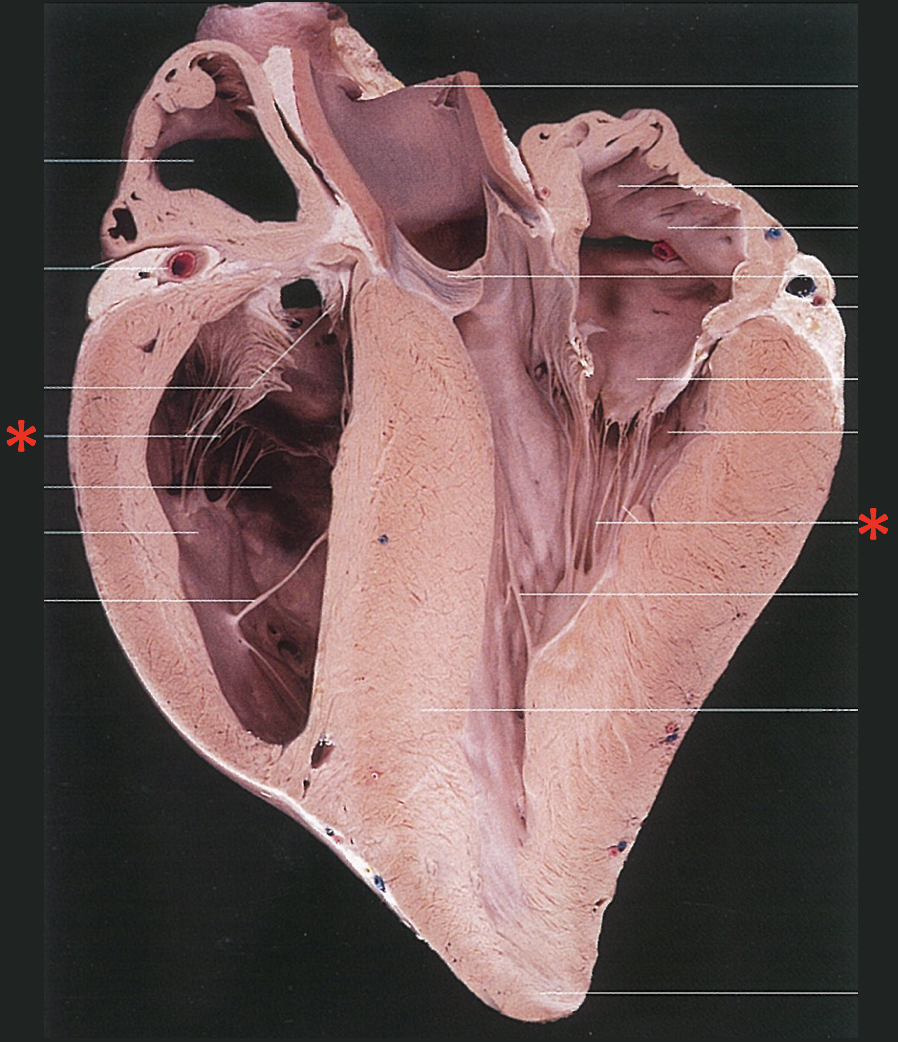

Chordae Tendinae

Left Muscular Band

Right Muscular Band

Muscular Ridges

Left Semilunar Valvula

Parietal Cup

Right Semilunar Valvula

Intermediate Semilunar Valvula

Septal Cusp

Right Ventricular Margin